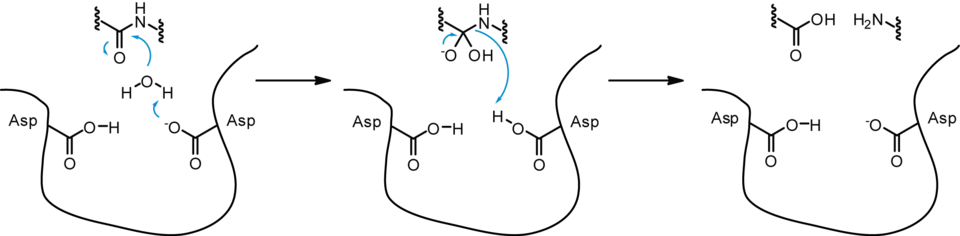

As an aspartic protease, the dimerized HIV-1 PR functions through the aspartyl group complex, in order to perform hydrolysis. Of the two Asp25 residues on the combined catalytic active site of HIV-1 PR, one is deprotonated while the other is protonated, due to pKa differences from the micro-environment.[16]

In a general aspartic protease mechanism, once the substrate is properly bound to the active site of the enzyme, the deprotonated Asp25 catalytic amino acid undergoes base catalysis, rendering the incoming water molecule a better nucleophile by deprotonating it. The resulting hydroxyl ion attacks the carbonyl carbon of the peptide bond, forming an intermediate with a transient oxyanion, which is stabilized by the initially protonated Asp25. The oxyanion re-forms a double bond, leading to the cleavage of the peptide bond between the two amino acids, while the initially deprotonated Asp25 undergoes acid catalysis to donate its proton to the amino group, making the amino group a better leaving group for complete peptide bond cleavage and returning to its original deprotonated state.[2][17]

While HIV-1 PR shares many of the same characteristics as a non-viral aspartic protease, some evidence has shown that HIV-1 PR catalyzes hydrolysis in a concerted manner; in other words, the nucleophilic water molecule and the protonated Asp25 simultaneously attack the scissile peptide bond during catalysis.[17][18]